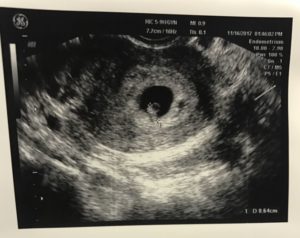

Фото узи 5 6 недель беременности фото

На этом сроке с диагностической целью часто проводится ультразвуковое исследование: оценивается диаметр плодного яйца (6 мм – норма для этого срока), его расположение (место имплантации).

В этот период женщина уже отмечает изменения своего самочувствия, но окружающим пока это не заметно. Животик еще не увеличился, матка достигает размера сливы. Малыш еще совсем маленький: сейчас это плодное яйцо 6-7 мм.

При проведении трансвагинальной эхографии (наиболее распространенный метод гинекологического УЗИ – через влагалище) при наличии маточной беременности определяется округлое анэхогенное образование – плодное яйцо 6-7 мм, расположенное в толще эндометрия.

Внутри плодного яйца визуализируются две полости, которые находятся одна в другой. Это первичный желточный мешок, а также полость внезародышевого целома. Визуализация плодного яйца возможна со срока беременности 4-5 недель.

На пятой неделе беременности эмбрион размером около 5 мм расположен около стенки желточного мешка. Желточный мешок визуализируется как кистозное образование с наличием анэхогенного содержимого. Эмбрион в желточном мешке находится эксцентрично, создавая характерную ультразвуковую картину «двойного пузыря».

Несмотря на то, что большинство органов эмбриона на данном сроке уже сформировано, их визуализация при ультразвуковом исследовании еще весьма затруднительна. Поэтому УЗИ на сроке 5-6 недель проводится не с целью определить, нормально ли развивается малыш, а с целью подтверждения беременности.